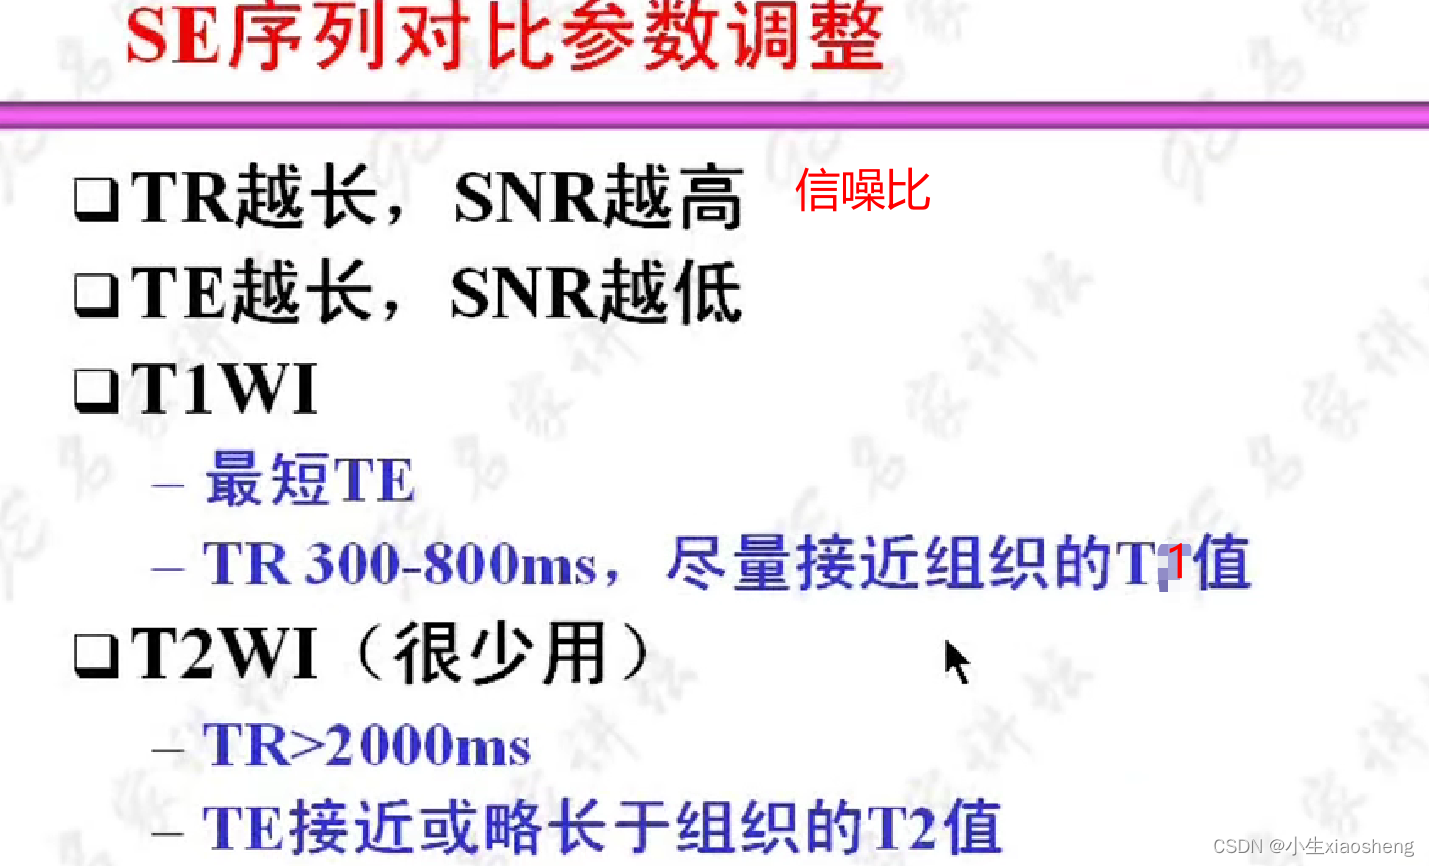

TR代表重复时间(repetition time),是指脉冲序列执行所需的时间

TE代表回波时间(echo time),是指产生宏观横向磁化矢量的脉冲中点到回波中点的时间间隔

选择合适长的TE获得最好的T2对比:一般TE选择两种组织生物T2值附近可获得最好的T2对比。

选择合适短的TR获得最好的T1对比:一般TR选择两种组织生物T1值附近可获得最好的T1对比。